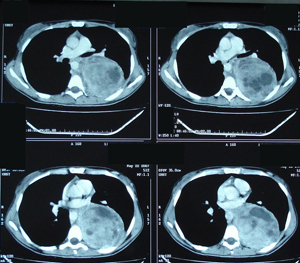

Εικόνα 3 α-δ

Αξονική τομογραφία του θώρακος. Επιβεβαιώνει τα ευρήματα της ακτινογραφίας του θώρακος. Δείχνει μάζα μαλακών μορίων, με νεκρώσεις, στο οπίσθιο μεσοθωράκιο χωρίς σημεία διήθησης παρακείμενων οργάνων.

A-B

Γ-Δ